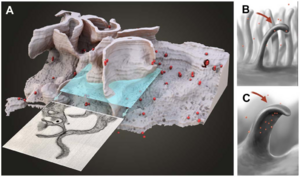

High Contrast Microstructural Visualization of Natural Acellular Matrices by Means of Phase-Based X-Ray Tomography

Publication: Sci Rep. 2015 Dec 14;5:18156. PMID: 26657471 | PDF Authors: Hagen CK, Maghsoudlou P, Totonelli G, Diemoz PC, Endrizzi M, Rigon L3, Menk RH, Arfelli F, Dreossi D, Brun E, Coan P, Bravin A, De Coppi P, Olivo A. Institution: University College London, Department of Medical Physics and Biomedical Engineering, London, UK. Background/Purpose: Acellular scaffolds obtained via decellularization are a key instrument in regenerative medicine both per se and to drive the development of future-generation synthetic scaffolds that could become available off-the-shelf. In this framework, imaging is key to the understanding of the scaffolds' internal structure as well as their interaction with cells and other organs, including ideally post-implantation. Scaffolds of a wide range of intricate organs (esophagus, lung, liver and small intestine) were imaged with x-ray phase contrast computed tomography (PC-CT). Image quality was sufficiently high to visualize scaffold microarchitecture and to detect major anatomical features, such as the esophageal mucosal-submucosal separation, pulmonary alveoli and intestinal villi. These results are a long-sought step for the field of regenerative medicine; until now, histology and scanning electron microscopy have been the gold standard to study the scaffold structure. However, they are both destructive: hence, they are not suitable for imaging scaffolds prior to transplantation, and have no prospect for post-transplantation use. PC-CT, on the other hand, is non-destructive, 3D and fully quantitative. Importantly, not only do we demonstrate achievement of high image quality at two different synchrotron facilities, but also with commercial x-ray equipment, which makes the method available to any research laboratory. Funding:

|

Images acquired with synchrotron-based PC-CT showing a rat small intestine that was decellularized via DET: (a) transverse cross section, (b) three-dimensional view. All scale bars represent 500 μm. Images were processed using the ESRF in-house software PyHST, and analyzed and displayed with ImageJ31 and 3D Slicer. |